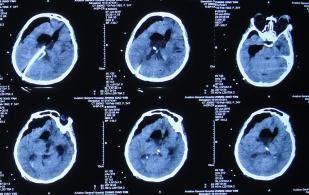

在第2家医院继续腰大池持续引流治疗1个月期间,曾多次查头部CT:2015年10月21日(图-15),2015年10月26日(图-16),2015年11月13日(图-17)均示脑室扩张反而越来越重。

图-15:2015年10月21日头部CT

图-16:2015年10月26日头部CT

图-17:2015年11月13日头部CT